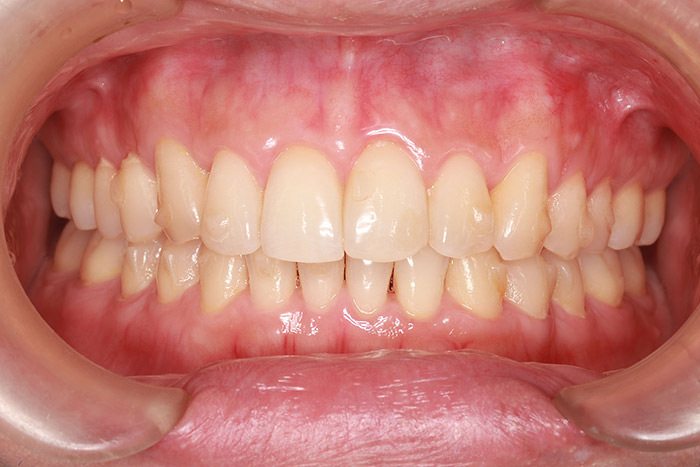

after

年齢 31歳

性別 女性

治療名称 マウスピース型カスタムメイド矯正歯科装置(インビザライン)・コンプリヘンシブパッケージ(難症例)

総額治療費用 935,000円(税込10%) 金額備考 精密検査料・診断料 33,000円(税込10%)

治療期間 3年4か月 通院頻度など 1か月ごと(途中から3~4か月ごと)

マウスピースの装着時にホワイトニングを兼用

ホームホワイトニング 両顎 30,800円(税込10%)

患者の症状 叢生、正中のずれ、上顎左右側切歯の口蓋側転位(交叉咬合)

治療方法 非抜歯で、マウスピース型カスタムメイド矯正歯科装置(インビザライン)による矯正

歯列弓を拡大することで非抜歯を可能にしました。

治療結果 側切歯の交叉咬合は解消、上下正中のずれも改善し咬み合わせが良くなりました。

※治療結果は患者様によって個人差があります。

転勤されため、途中から通院間隔が延びました。

リスク/副作用 1日22時間以上、装置の装着時間が必要です。